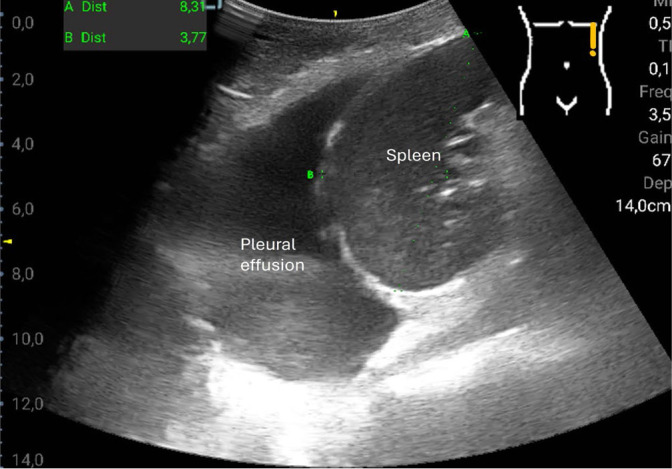

Results: The most common pathological findings were renal cysts in 34/120 (28.3%), left-sided or right-sided pleural effusions in 33/120 (27.5%) and 29/120 (24.2%) patients, respectively, dilatation of the vena cava in 24/120 (20.0%), and urinary retention in 14/120 (11.7%) patients. In 13/120 (10.8%) patients, the sonographic examination resulted in a diagnostic consequence, while in 38/120 (31.7%) patients in a therapeutic consequence. Among the false-negative findings using the hand-held ultrasound device, no finding was of therapeutic relevance. Four findings that were missed by the hand-held ultrasound device were diagnostically significant: two lesions of the kidney, one lesion of the liver, and one case of urinary stasis kidney.

Conclusions: With the hand-held ultrasound device, only 33 of 52 focal lesions were detected. Thus, a high-end ultrasound device cannot be replaced by a hand-held ultrasound device for this purpose, but certain clinical questions can be answered reliably with a hand-held ultrasound device (such as the presence of a puncture-worthy pleural effusion in patients with dyspnea, or verification of the volume status based on the diameter of the vena cava).

Abstract Image